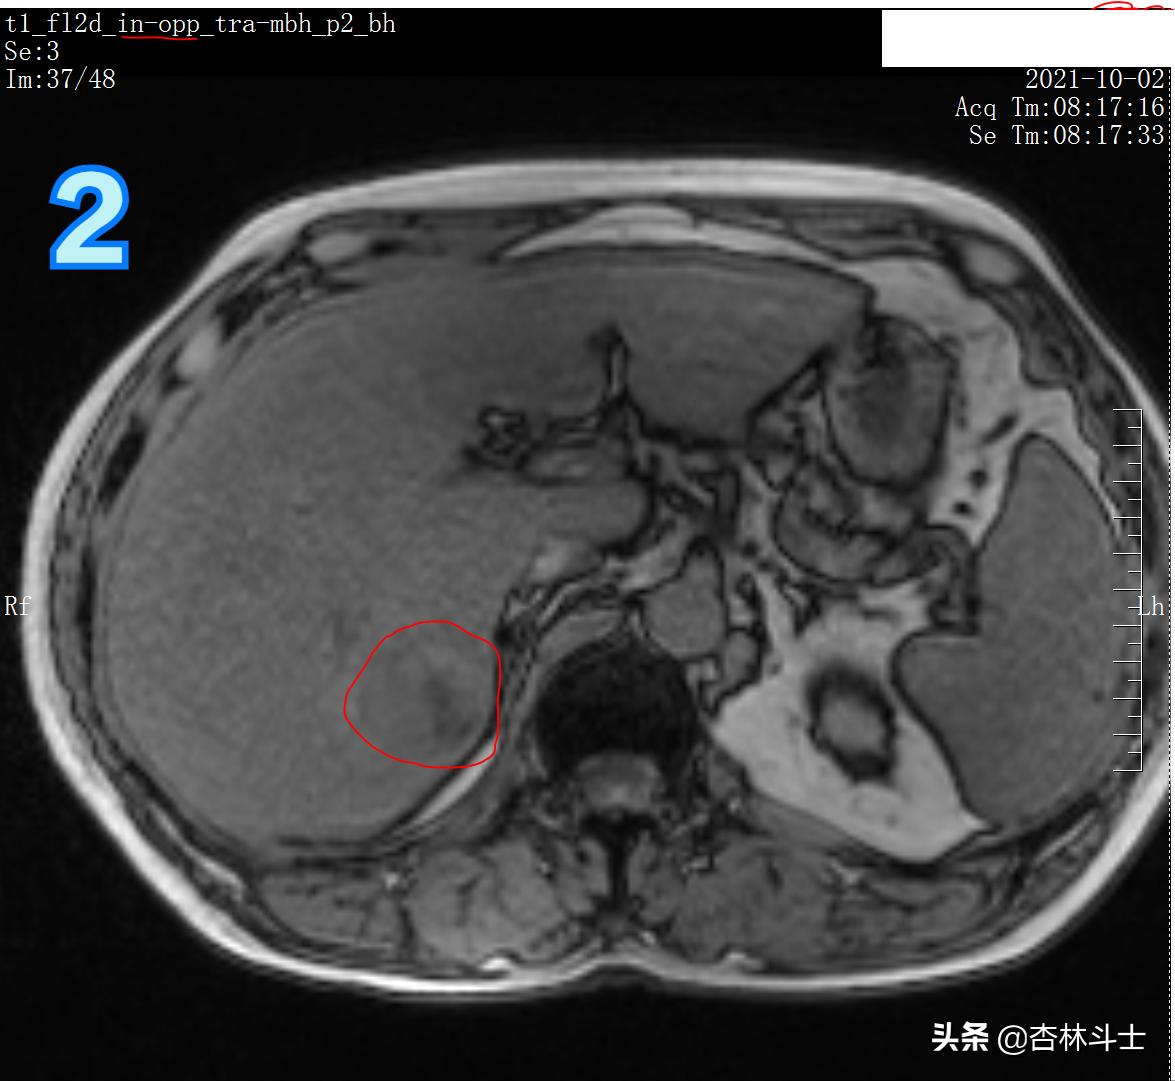

图2 T1加权反相位

图1-3为T1加权图像,同一台3T磁共振机器上做的,与1月22日的信号明显不同,说明病灶里面的成分有所变化。